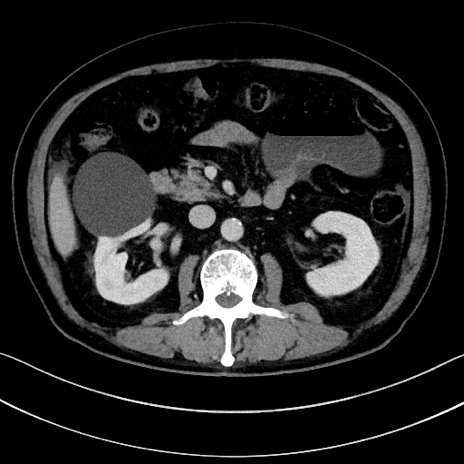

症例15(横断像)

【症例】70歳代男性

【主訴】腹痛

【現病歴】今朝から腹痛あり。全体的に痛い。特に左上の方。排ガスが今日はない。冷や汗が出る。

【既往歴】直腸癌術後

【身体所見】左側腹部〜上腹部に圧痛あり。腹膜刺激症状明らかなではない。軽度反跳痛。左下腹部に術後瘢痕あり。

【データ】WBC 7700、CRP 0.02